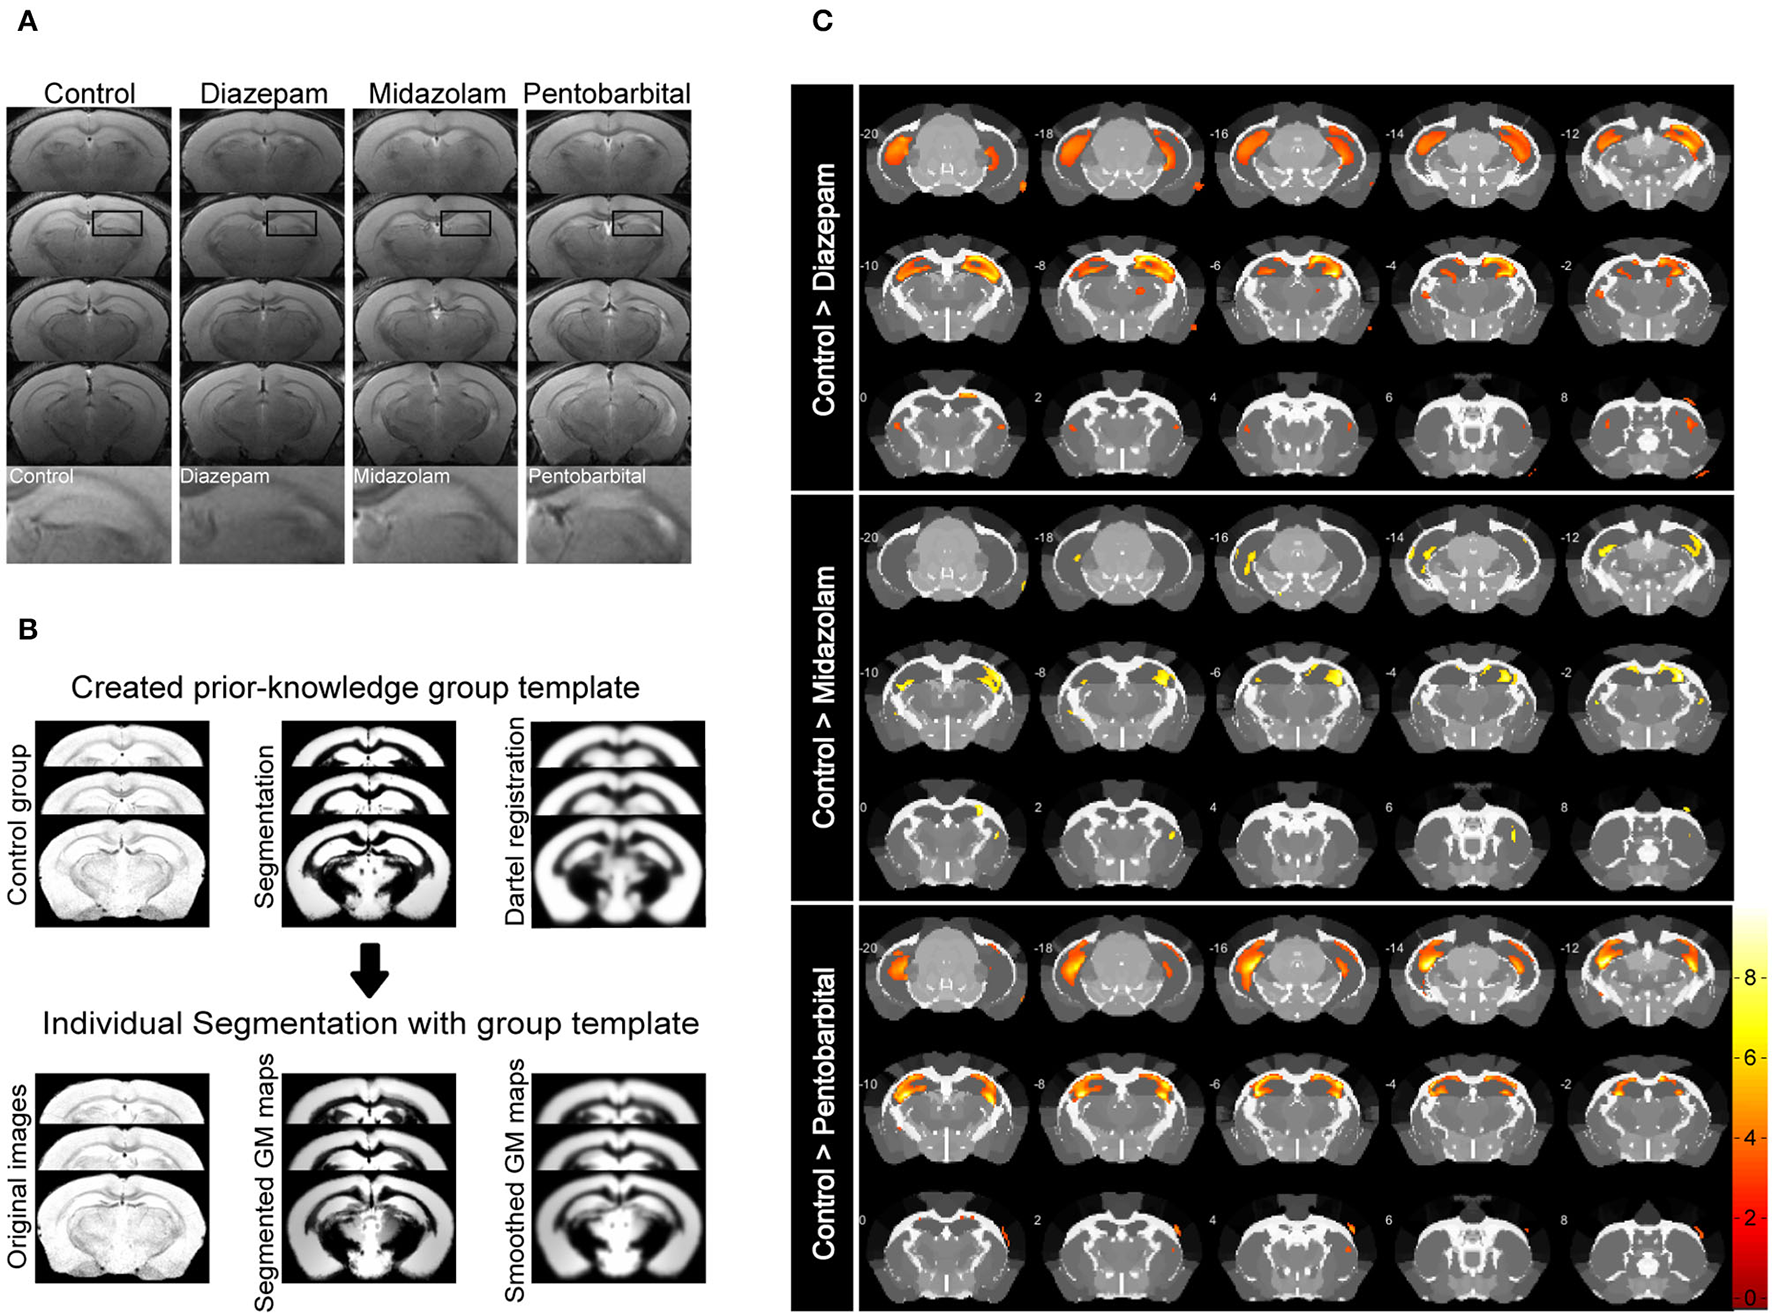

Magnetic resonance imaging (MRI) is able to reliably detect regional structural changes of the epileptic brain in relation to epileptogenesis of animal models (13, 14). Hippocampal atrophy is the most featured structural alternation of the pilocarpine-SE model of spontaneous chronic temporal epilepsy (13, 15, 16). To compare the long-term effects of diazepam, midazolam, and pentobarbital treatments antagonizing SE on brain structural changes, we performed MRI 9 weeks after SE induction. T2-weighted images showed that SE induction chronically causes hippocampal atrophy indicated by the shrinked hippocampal volume in all the treatment groups of mice when compared with the control group of mice that failed to be induced SE by pilocarpine (Figure 3A). However, voxel-based morphometry (VBM) analysis of T2-weighted images showed that midazolam treatment causes relatively less hippocampal sclerotic atrophy when compared to diazepam and pentobarbital treatments (Figures 3B,C and Table 1), suggesting that midazolam treatment against SE leads to less structural damages.

Figure 3

Voxel-based morphometry (VBM) analysis of MRI T2-weighted images showing differential hippocampal atrophy 9 weeks after SE received different treatments. (A) Hippocampal T2 maps along the rostro-caudal axis (up-down) showing sclerotic atrophy of hippocampus of control (non-SE and no treatment), diazepam, midazolam, and pentobarbital groups of mice after SE. The images in the lowest row are the amplifications of areas in the rectangle of the second row of images. (B) The template creation for spatial normalization of the segmented gray matter (GM) images and VBM procedure. (C) Each subfigure of the treatment group showed volumetric changes of GM when compared with corresponding subfigure of control group. Hippocampal GM densities in the midazolam group were significantly higher than other groups. The color scale bar on the right represents t-value of the statistical analysis. Control n = 6; diazepam n = 7; midazolam n = 7; and pentobarbital n = 4.